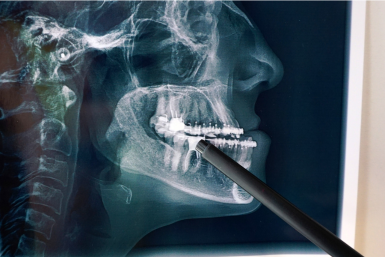

La cirugía oral y maxilofacial es esencial para tratar condiciones que afectan la cara, boca y mandíbulas. Algunas condiciones que hacen que los pacientes busquen este tipo de cirugía incluyen, colocar implantes dentales para remplazar dientes y corregir problemas en la mordida con cirugía ortognática, tratar trastornos de la ATM, y manejar condiciones severas como labio o paladar hendido y cáncer de boca. Estos problemas pueden afectar la función, la comodidad y la apariencia, lo que hace importante la intervención médica experta

El cirujano maxilofacial en Piedras Negras está calificado para tratar estos problemas diversos, combinando entrenamiento dental y quirúrgico. Realizan procedimientos que van desde injertos de hueso para preparar para implantes dentales, a complejas reconstrucciones faciales después de una lesión o remoción de un tumor. Para los pacientes que sufren de mandíbulas desalineadas, realizan cirugía mandibular precisa para mejorar la mordida y el perfil del rostro. Su especialización les permite restaurar la integridad estructural y estética de la región craneofacial, usualmente colaborando con otros especialistas para brindar un cuidado integral.